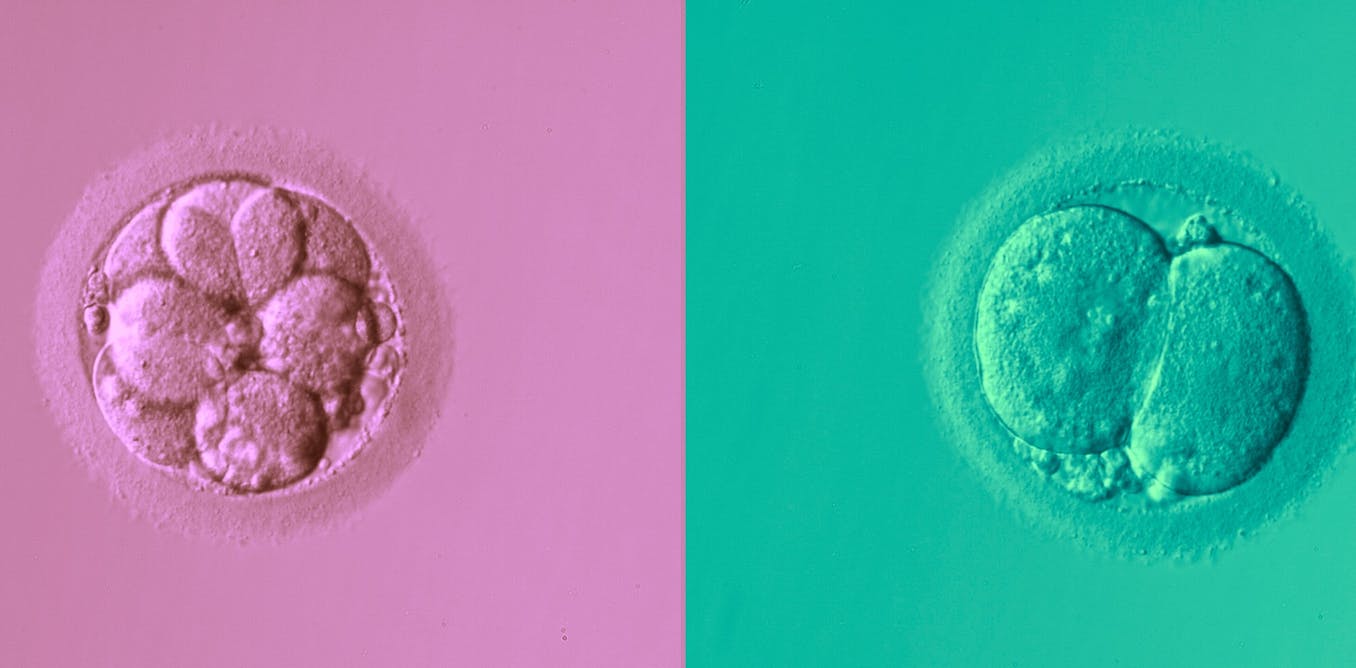

During in vitro fertilisation (IVF), a number of different embryos are produced from eggs and sperm. Then, embryologists choose which one of the embryos is most likely to lead to a successful pregnancy and transfer it to the patient.

Embryologists make this choice by using their expertise to apply a set of widely accepted principles based on the appearance of the embryo. In recent years there has been a lot of interest in using various artificial intelligence (AI) techniques in this process.